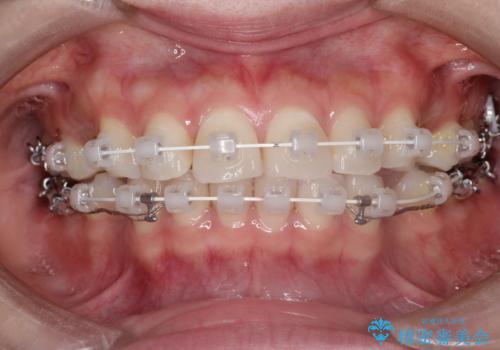

- 矯正装置

- 審美装置

- 治療期間

- 2年1ヶ月

- 治療回数

- 10-30回